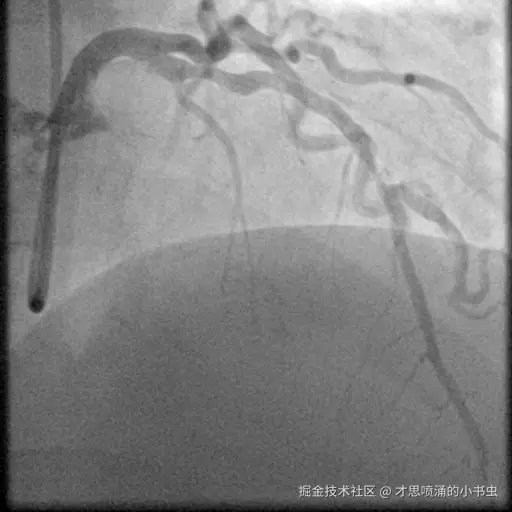

以下图像展示了每个模型在相同冠状动脉造影图像上的表现:

图5 DINO 的检测结果,结果更少但更精确。

3.1 DINO 检测模式

DINO 总体上检测结果较少,偶尔会错过相关的狭窄区域,但其检测到的区域通常都是准确的。这表明该模型学习了更严格的狭窄判断标准。例如,在某些测试案例中,DINO 以高置信度检测到单个狭窄区域,同时错过了更微妙的次要区域。这种模式在图 5 和图 8 中很明显,模型识别了主要狭窄区域但可能忽略了其他狭窄区域。

图8 DINO检测显示其倾向于更少、更精确的检测。